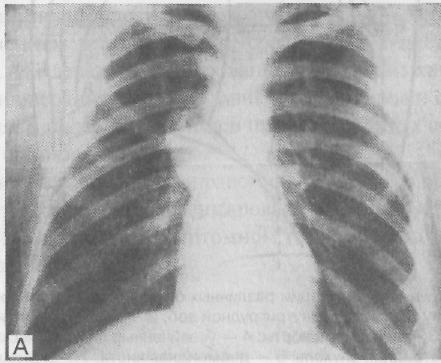

Для диагностики опухолей средостения (рис. 4.16) применяют многопроекционное рентгенологическое обследование, КТ. Решающую роль в диагностике играют КТ и УЗИ. Для морфологической

Рентгенограмма опухоли средостения. Наибольший диаметр тени опухоли совпадает с тенью средостения, края тени образуют со средостением тупые углы (рентгенологический симптом Ленка)

верификации опухоли проводят чрескожную биопсию под контролем КТ, а также УЗИ с применением конвексного датчика. В некоторых случаях применяют пневмомедиастинографию. По показаниям (сдавление бронхов или пищевода) используют бронхоскопию и эзофагоскопию, а также торакоскопию и медиастиноскопию. При синдроме верхней полой вены выполняют ангиографическое исследование (каваграфию).